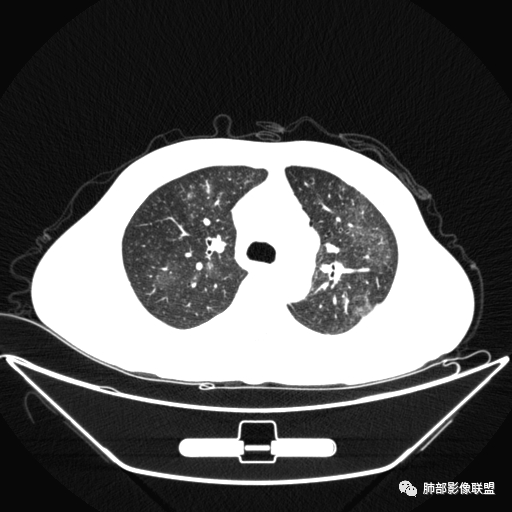

两肺多发团片状高密度影

南边:

边界模糊,距离胸膜有间隙,内部支气管通畅